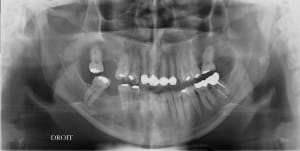

CHA_Ka_pano_du_03.10.2017_2153_wygydh.jpg